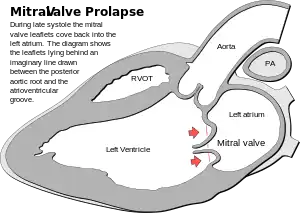

| Drawing of the leaflets of the mitral valve prolapsing back into the left atrium. | |

Mitral valve prolapse (MVP) is a valvular heart disease in which mitral valve leaflets enter into the left atrium when the ventricle contracts.[1] Symptoms vary from none, to chest pain, shortness of breath, palpitations, and anxiety.[1][3] Complications may include mitral regurgitation, atrial fibrillation, infective endocarditis, stroke, and cardiac arrest.[1]